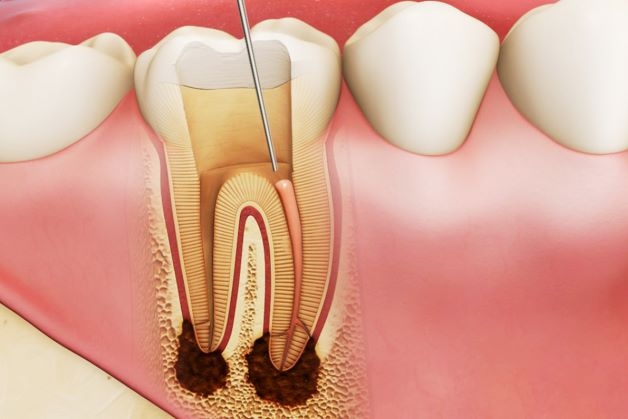

– Điều trị nội nha:

+ Làm sạch sẽ và tạo hình hệ thống ống tủy.

+ Đặt Ca(OH)2 trong ống tủy với mục đích làm trung hòa mô viêm vùng cuống, sát khuẩn hệ thống ống tủy.

+ Hàn kín ống tủy.

+ Phục hồi thân răng.

– Điều trị viêm quanh cuống răng bằng phương pháp phẫu thuật

+ Phương pháp này được áp dụng trong các trường hợp sau khi điều trị nội nha có tổn thương quanh cuống không thể phục hồi.

+ Răng sau khi được điều trị nội nha theo dõi những tổn thương cuống và không có tiến triển tốt thì cần phải tiến hành điều trị phẫu thuật nhằm lấy đi toàn bộ lớp vỏ nang. Nếu phải cắt bỏ cuống răng thì bác sĩ sẽ tiến hành hàn ngược cuống răng.